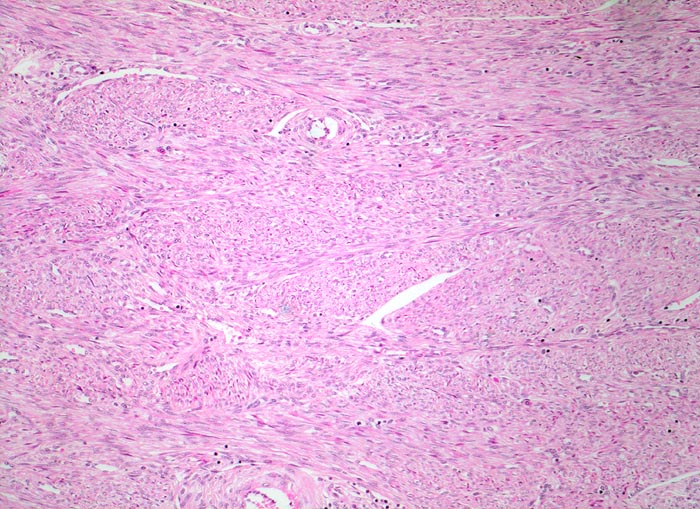

PathoPic ID 4811 - normales Myometrium

normales Myometrium

Myometrium

Genitalorgane, weiblich

Bündel von teils längs, teils quer getroffenen glatten Muskelfasern.

Hysterektomie wegen Meno/Methrorrhagien

Histologie

100

48